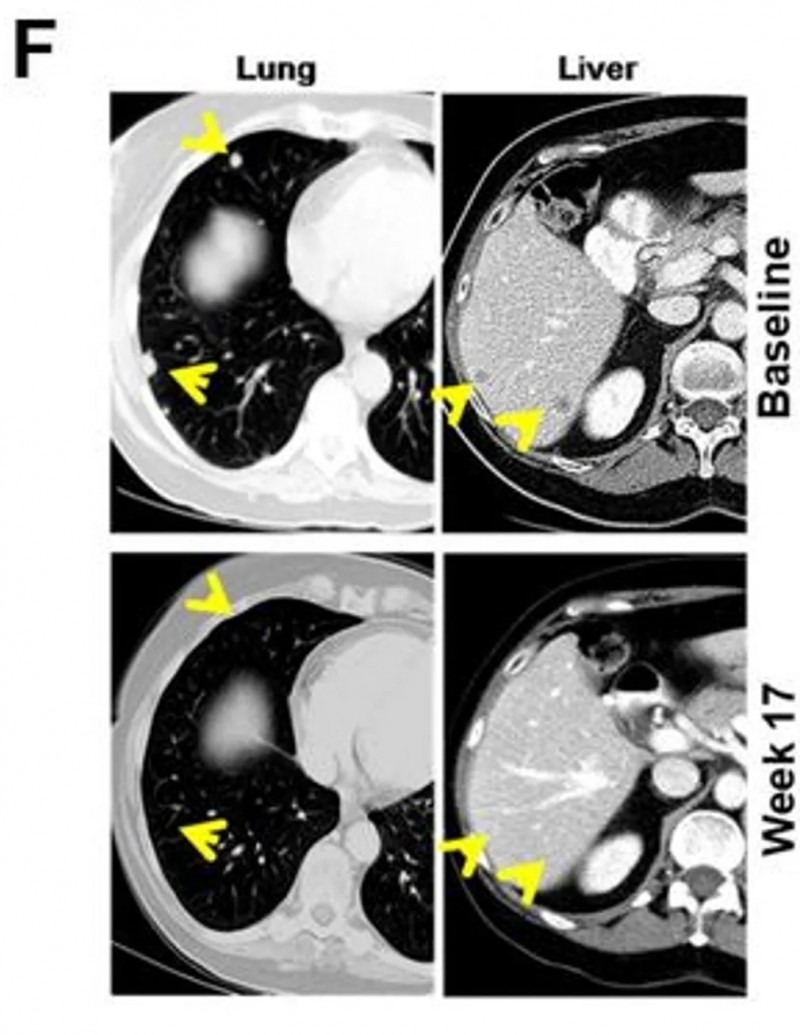

一项发表在《癌症免疫治疗杂志》上的前瞻性II期试验(NCT01876212)为联合治疗提供了证据。该研究针对15例PD-1抑制剂耐药的晚期黑色素瘤患者,使用“树突状细胞疫苗+达沙替尼”方案。

结果显示:从一开始就联合用药的B组,疗效远优于后期才联合的A组:客观缓解率达到66.7%,中位总生存期延长至15.45个月(对比3.47个月)。

值得一提的是,B组2例代表性患者经联合治疗后,内脏转移瘤明显缩小,并产生了协同免疫反应,最终达到客观部分缓解(PR)标准。

▲图源“JITC”,版权归原作者所有,如无意中侵犯了知识产权,请联系我们删除